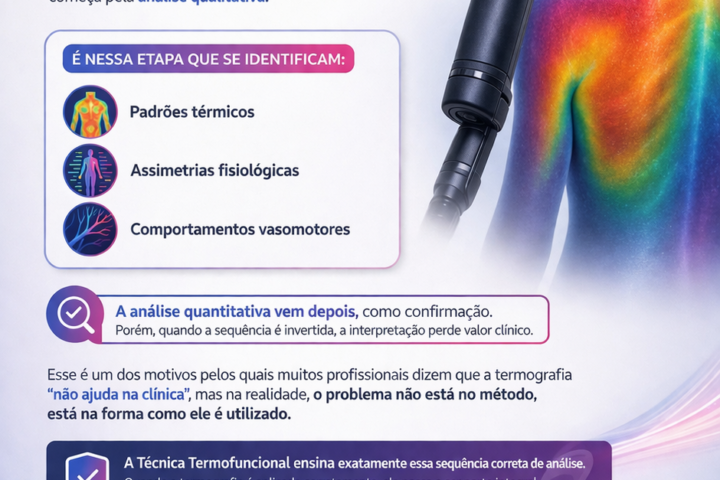

Somente com o conhecimento integral do Método de Termografia Infravermelha é possível detectar alterações e associá-las a uma disfunção.